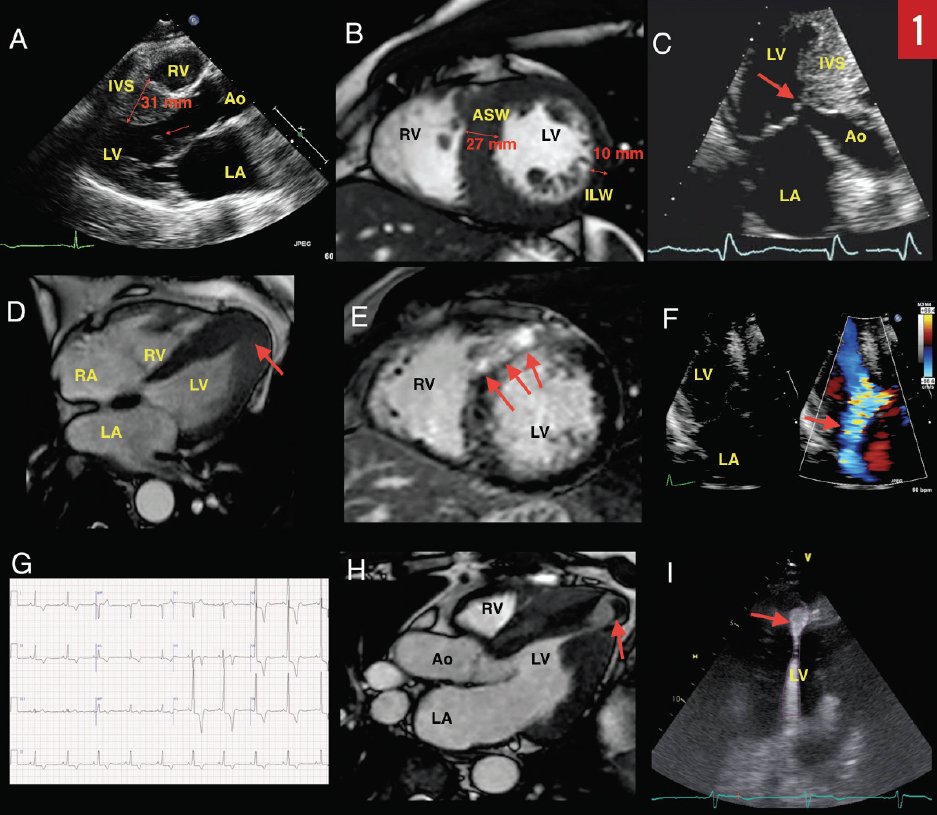

Electrocardiography (ECG). A 12-lead ECG is recommended during the initial evaluation of all patients with suspected or confirmed HCM. The ECG may show findings of left ventricular hypertrophy (LVH) based on voltage criteria (Sokolov-Lyon criteria are most commonly used—ie, S wave depth in lead V1 or V2 + tallest R wave height in lead V5 or V6 ≥ 35 mm) and widespread Q waves.3,4 These abnormalities, however, do not correlate with severity or pattern of hypertrophy as determined by echocardiography. The exception is with apical variant HCM, where LVH and deep inverted T waves can be seen in leads V2 through V6 as well as in leads II, III, and aVL (Yamaguchi pattern, Figure 1G).5 A normal ECG can be observed in 5% to 10% of patients with HCM; therefore, ECG alone cannot be used to rule out HCM.4

Transthoracic echocardiography (TTE). Echocardiography is the primary modality for evaluating and monitoring patients with suspected or confirmed HCM. Traditionally, morphologic diagnosis is based on the presence of hypertrophy (≥ 15 mm) in the absence of other potential systemic causes for hypertrophy, such as longstanding hypertension or athlete’s heart.3 Milder hypertrophy (> 13 mm) is sometimes considered diagnostic in patients with a positive family history or if other features of HCM are present.6,7 Classically, the basal anteroseptum is involved, but various patterns of hypertrophy involving other areas, as well as diffuse hypertrophy, have also been described.8 A focused view of the apex may identify localized apical hypertrophy (ie, apical variant HCM), which may have associated apical aneurysm (Figure 1D). If present, this can lead to thrombus formation and predispose to thromboembolic events or stroke (Figure 1H).

Systolic anterior motion (SAM) of the mitral valve (MV) leaflets is characteristic in hypertrophic obstructive cardiomyopathy (HOCM) and results in characteristic dynamic LVOT obstruction and posteriorly directed mitral regurgitation (MR) (Figures 1A, 1C, and 1F). HCM with significant obstruction at rest (> 30 mm Hg), with provocation, or with exercise (> 50 mm Hg) is present in the majority of patients, with prevalence of up to 70% (Figure 2A).15 Obstruction results from a variety of mechanisms, including narrowing of the outflow from septal hypertrophy, papillary muscle displacement, and elongated MV leaflets.16,17 SAM-septal contact results in a pressure gradient between the LV and the aorta at the subvalvular level and was the very first physiologic abnormality described in the 1950s, resulting in the initial term idiopathic hypertrophic subaortic stenosis.18 Today, it is known that obstruction may occur in the midcavity or apical regions depending on the location of the hypertrophy. In the United States, apical variant HCM is rare and has been noted in 1% to 2% of cases; however, in Japan and other Asian countries, it is more common.8,19,20

Tissue Doppler imaging (TDI). TDI is a useful technique for differentiating HCM from athlete’s heart. Athlete’s heart tends to show normal or super-normal values, whereas there is evidence of abnormal myocardial mechanics in patients with HCM.21 Contemporary evaluation of mechanics using myocardial deformation imaging (strain imaging) suggests that HCM patients have reduced longitudinal but increased circumferential strain.22 LV opacification with contrast echocardiography is important for detecting the presence of apical variant HCM, LV aneurysms, and LV thrombus (Figure 1I). Additionally, contrast echocardiography is used intraprocedurally for the delineation of the perfusion territory of isolated septal perforator arteries prior to alcohol septal ablation (ASA).23 Tissue characterization using myocardial contrast echocardiography is an area of active research.

Cardiovascular magnetic resonance imaging (MRI). Cardiovascular MRI has emerged as a vital tool in contemporary management of HCM patients. Stunningly resolute images provide precise localization of hypertrophy, evaluation of the MV apparatus, papillary muscle morphology, and prognostic information from quantification of myocardial fibrosis (Figure 1E).31,32 Cardiovascular MRI has been useful for differentiation of HCM from phenocopies such as hypertensive heart disease, athlete’s heart, and infiltrative and metabolic cardiomyopathies (Figure 1B). Cardiovascular MRI is vital for operative planning and has been used for 3-dimensional printing in order to facilitate this.33